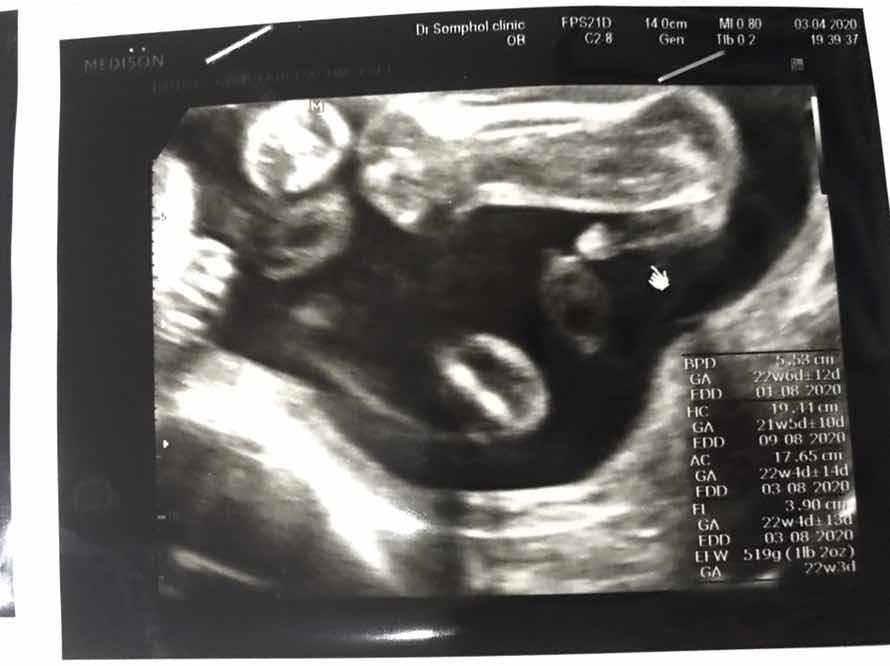

กำหนดคลอด6สิงหาจ้า ผู้ชายค่ะดิ้นแรงมากแข็งแรงมากค่ะ 22+5วีคค่ะ